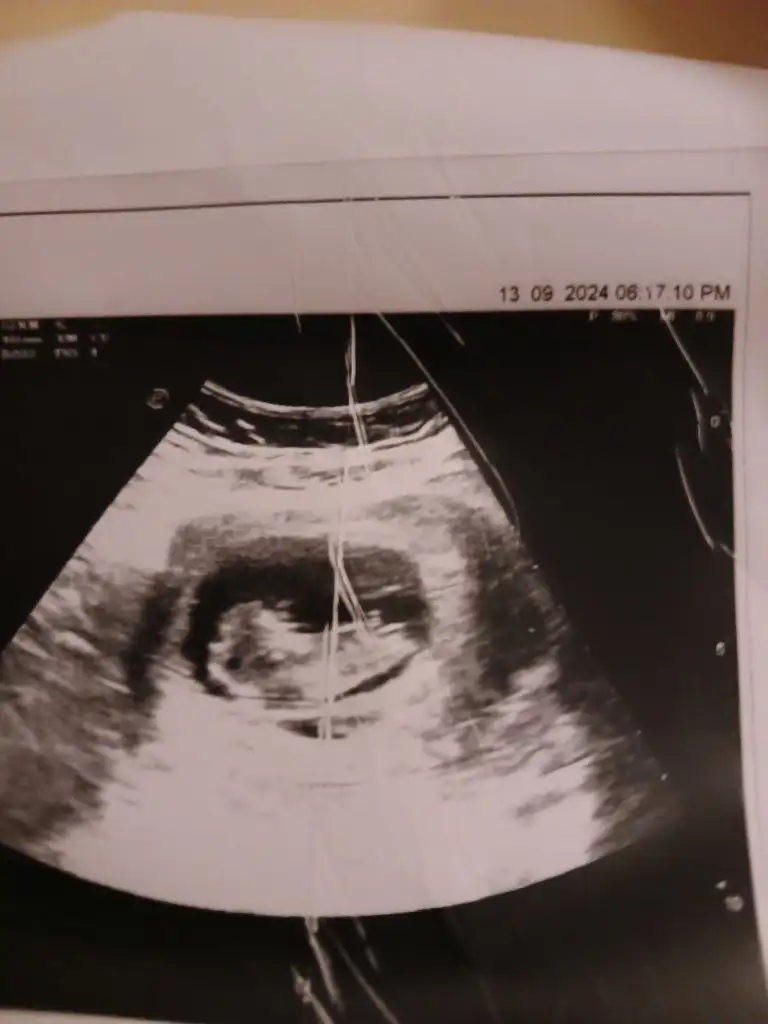

Kimse yok mu12 haftalik karindan ultrason rica etsem cinsiyet tahmini yapabilir misiniz

Başka foto yok mi12 haftalik karindan ultrason rica etsem cinsiyet tahmini yapabilir misiniz

Bacak arası fotosu bu doktor kız diyor ama ben hala erkek hissediyorummmCanım hiç belli olmuyor bacak kısımları anlayamayuz böyle

Evet doktor kız dedi ama ben ısrarla erkek hissediyorummm 14. Haftada söylediBence kız bir an öyle hissettim nedenini bilmeden ama tabi ne olursa olsun sağlıklı olsun

Evet doktor kız dedi ama ben ısrarla erkek hissediyorummm 14. Haftada söyledi

Bacak arasını boş gördüğü için demiştir kızda yanılma payı var detaylı ultrasona girene kadar bende erkek hissediyorum ama daha belli değil 15 hafta 2 günlük benim bebişim deEvet doktor kız dedi ama ben ısrarla erkek hissediyorummm 14. Haftada söyledi